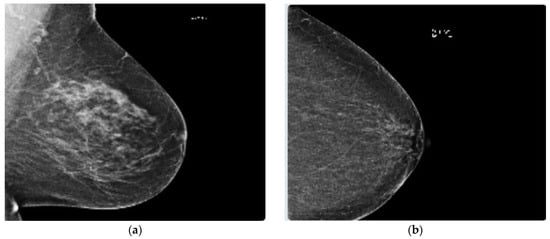

- The mammographic image analysis society (MIAS) [23] dataset is a well-known and widely used dataset for the development and evaluation of CAD systems for BC detection. It consists of 322 mammographic images, with each image accompanied by a corresponding ground truth classification of benign or malignant tumors. The dataset is particularly valuable for researchers interested in developing machine learning algorithms for BC detection, as it includes examples of both normal and abnormal mammograms, as well as a range of breast densities and lesion types. Figure 2 depicts two sample images from this dataset for cancer and normal cases.